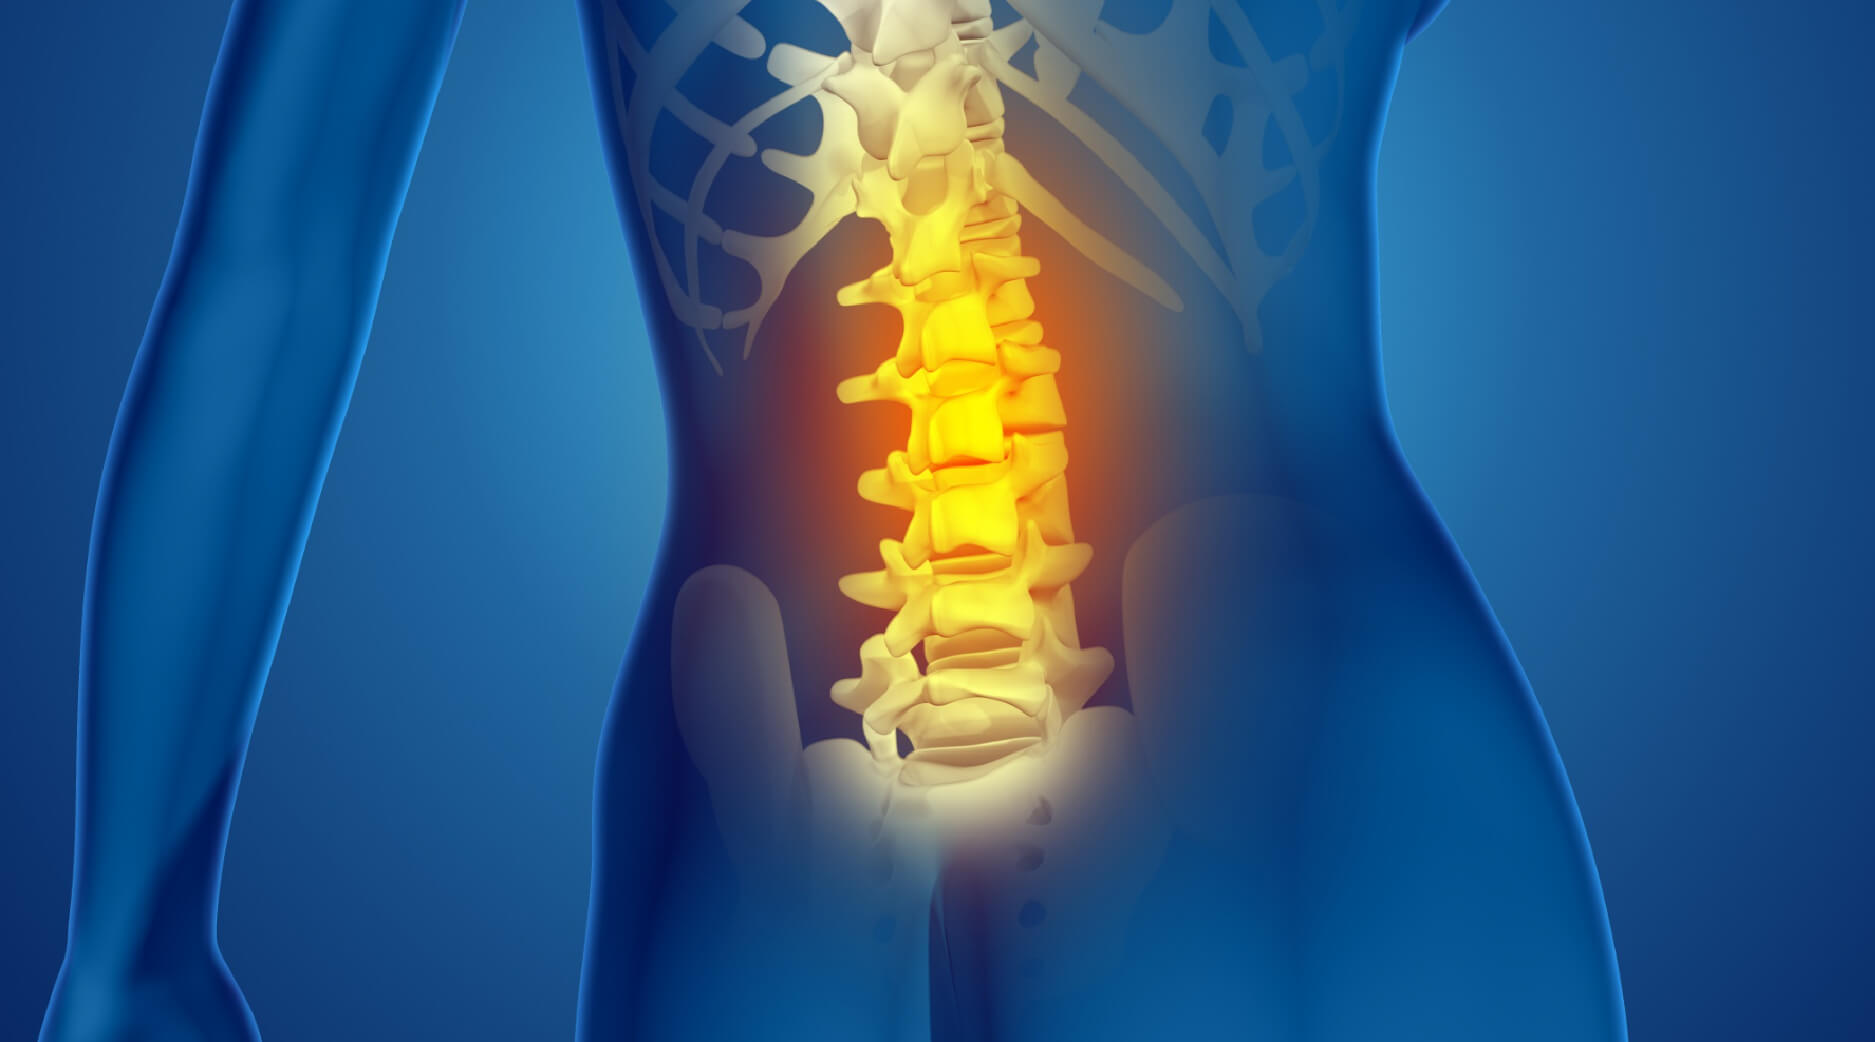

অনেকেরই কোমর থেকে ব্যথা পায়ের দিকে ঝিঁঝিঁ করে নেমে যায়। এই সমস্যার অন্যতম প্রধান কারণ হলো পিএলআইডি বা ডিস্ক প্রলাপস।

আমাদের মেরুদণ্ডের হাড়গুলোর মাঝখানে জেলির মতো ‘ডিস্ক’ থাকে। যখন এই ডিস্কটি বের হয়ে এসে পাশের স্নায়ু বা সায়াটিক নার্ভে চাপ দেয়, তখন কোমর ও পায়ে প্রচণ্ড ব্যথা শুরু হয়। একেই সাধারণত সায়াটিকা বলা হয়।

উপসর্গগুলো কী কী?

কোমরে প্রচণ্ড ব্যথা যা পায়ের দিকে ছড়িয়ে যায়।

পা ঝিঁঝিঁ করা, অবশ ভাব বা জ্বালাপোড়া করা।

বেশিক্ষণ বসে থাকলে বা হাঁটলে ব্যথা বেড়ে যাওয়া।

মারাত্মক ক্ষেত্রে প্রস্রাব-পায়খানার নিয়ন্ত্রণ হারানো বা পা চিকন হয়ে যাওয়া।

চিকিৎসা:

প্রাথমিক অবস্থায় বিশ্রাম ও ফিজিওথেরাপিতে কাজ হলেও, যদি স্নায়ুতে চাপ বেশি থাকে তবে দেরি করা বিপজ্জনক। আধুনিক ‘মাইক্রো-ডিস্কেকটমি’ বা ‘মিনিমাল ইনভেসিভ’ পদ্ধতিতে এখন খুব সহজেই স্নায়ুর চাপ সরিয়ে ফেলা যায়, যা ব্যথার স্থায়ী সমাধান দেয়।